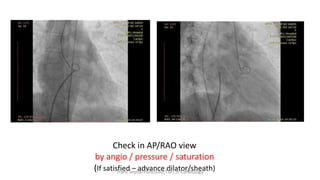

Check in AP/RAO view

by angio / pressure / saturation

(If satisfied – advance dilator/sheath)